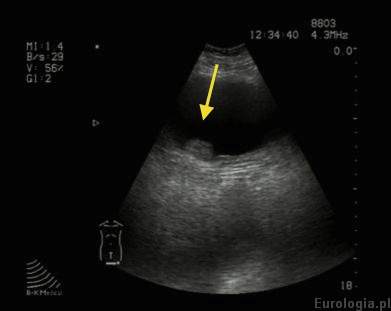

Fot. Guz pecherza okolicy ujścia prawego moczowodu średnicy 14 mm widoczny w USG

Obraz USG guza pęcherza moczowego